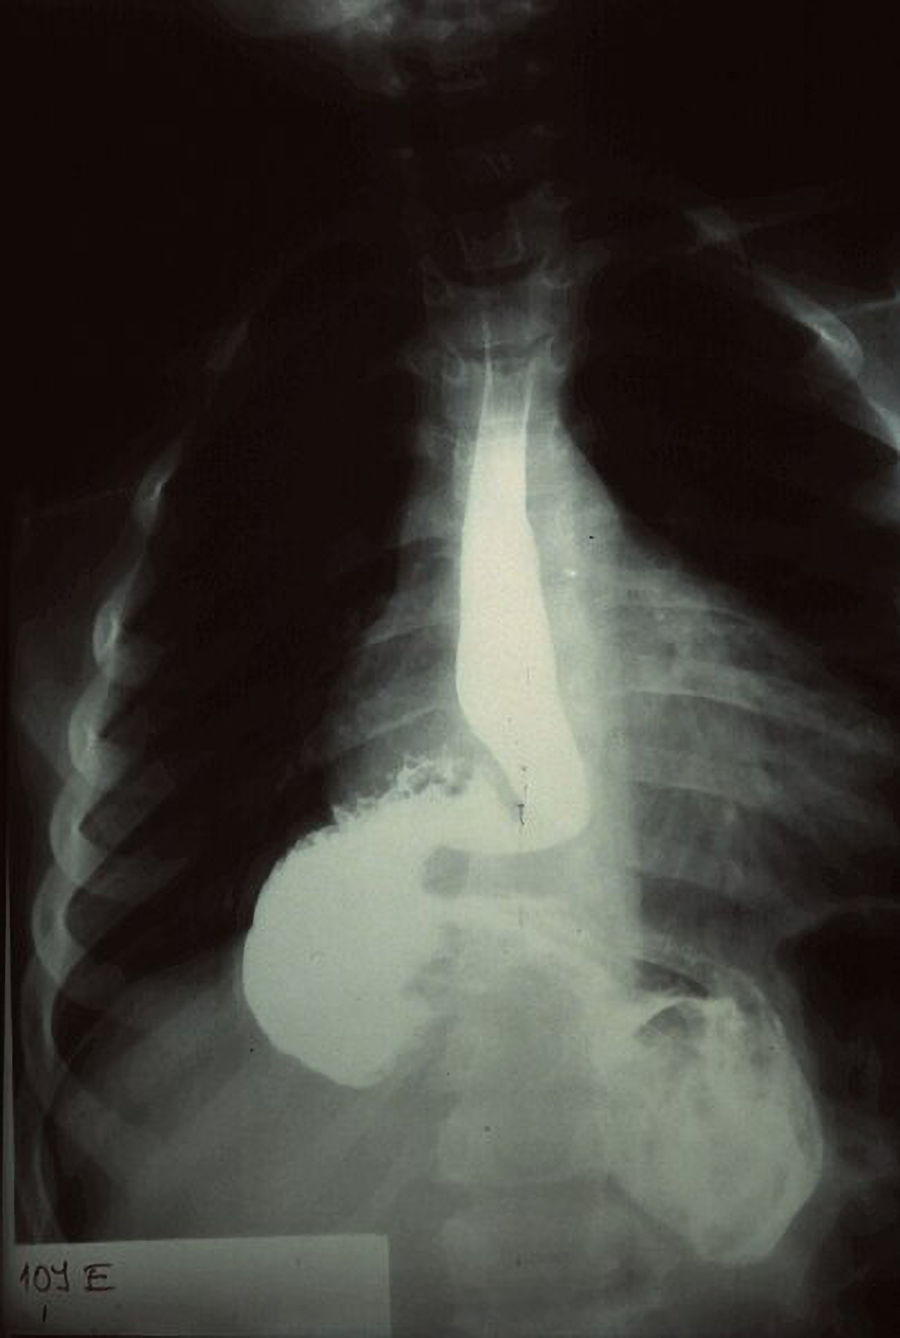

An upper gastrointestinal series (upper GI series) is an X-ray examination of the upper gastrointestinal (GI) tract. This testing can be used to detect esophageal cancer, among other uses. The esophagus, stomach, and duodenum are made visible on X-ray film by a liquid suspension that may be barium or a water-soluble contrast. If only the pharynx and esophagus are examined with barium, the procedure is called a barium swallow. Barium is a chalky material that appears white on X-ray and coats the inner walls of the digestive tract when administered. Fluoroscopy is often used during an upper GI series to allow the radiologist to visualize the movement of the barium through the esophagus, stomach, and duodenum as a person drinks. After the procedure, if barium is not completely eliminated from the body, constipation and fecal impaction can occur.

The figure below shows an image of an upper GI series that shows a hernia and an obstruction. The barium causes the stomach and esophagus to appear white. Narrowing represents the obstruction.